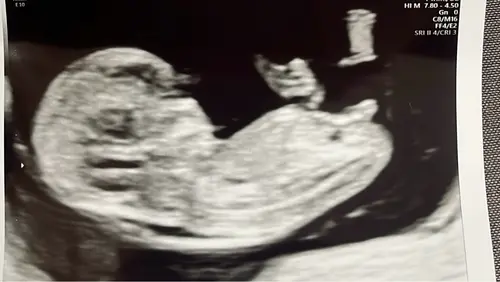

Hay! Dit is de 12 weken echo

Hoi allemaal! Is dit dan een meisje? Omdat het redelijk recht lijkt?

Nu nog een meisje, maar kan veranderen tot en met week 13